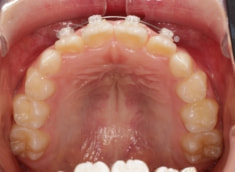

症例紹介

小児期ケース:叢生(ガタガタ)

治療法:拡大プレート+フルパッシブブラケット(クリアスナップ)

治療後(8ヶ月後)